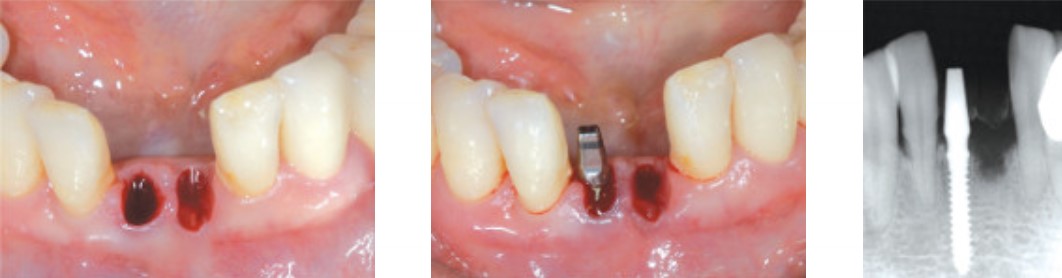

Пациент: 51 год, женщина

Состояние: Пародонтит

#31 шатается, рецессия десны

Продукт: Имплантат для узкого гребня MS

Размеры: Φ 2.5 * 13 mm

Панорамный снимок и фотография ротовой полости

Экстракция, #41 Имплантат для узкого гребня MS